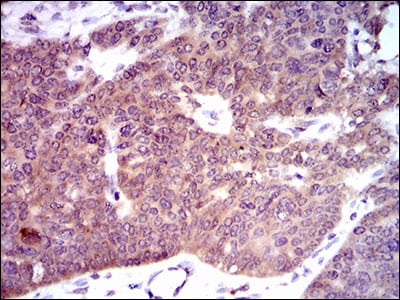

分类: 科研抗体货号: 30464A别名: PDE1B1; PDES1B应用: IHC,FCM反应种属: Human